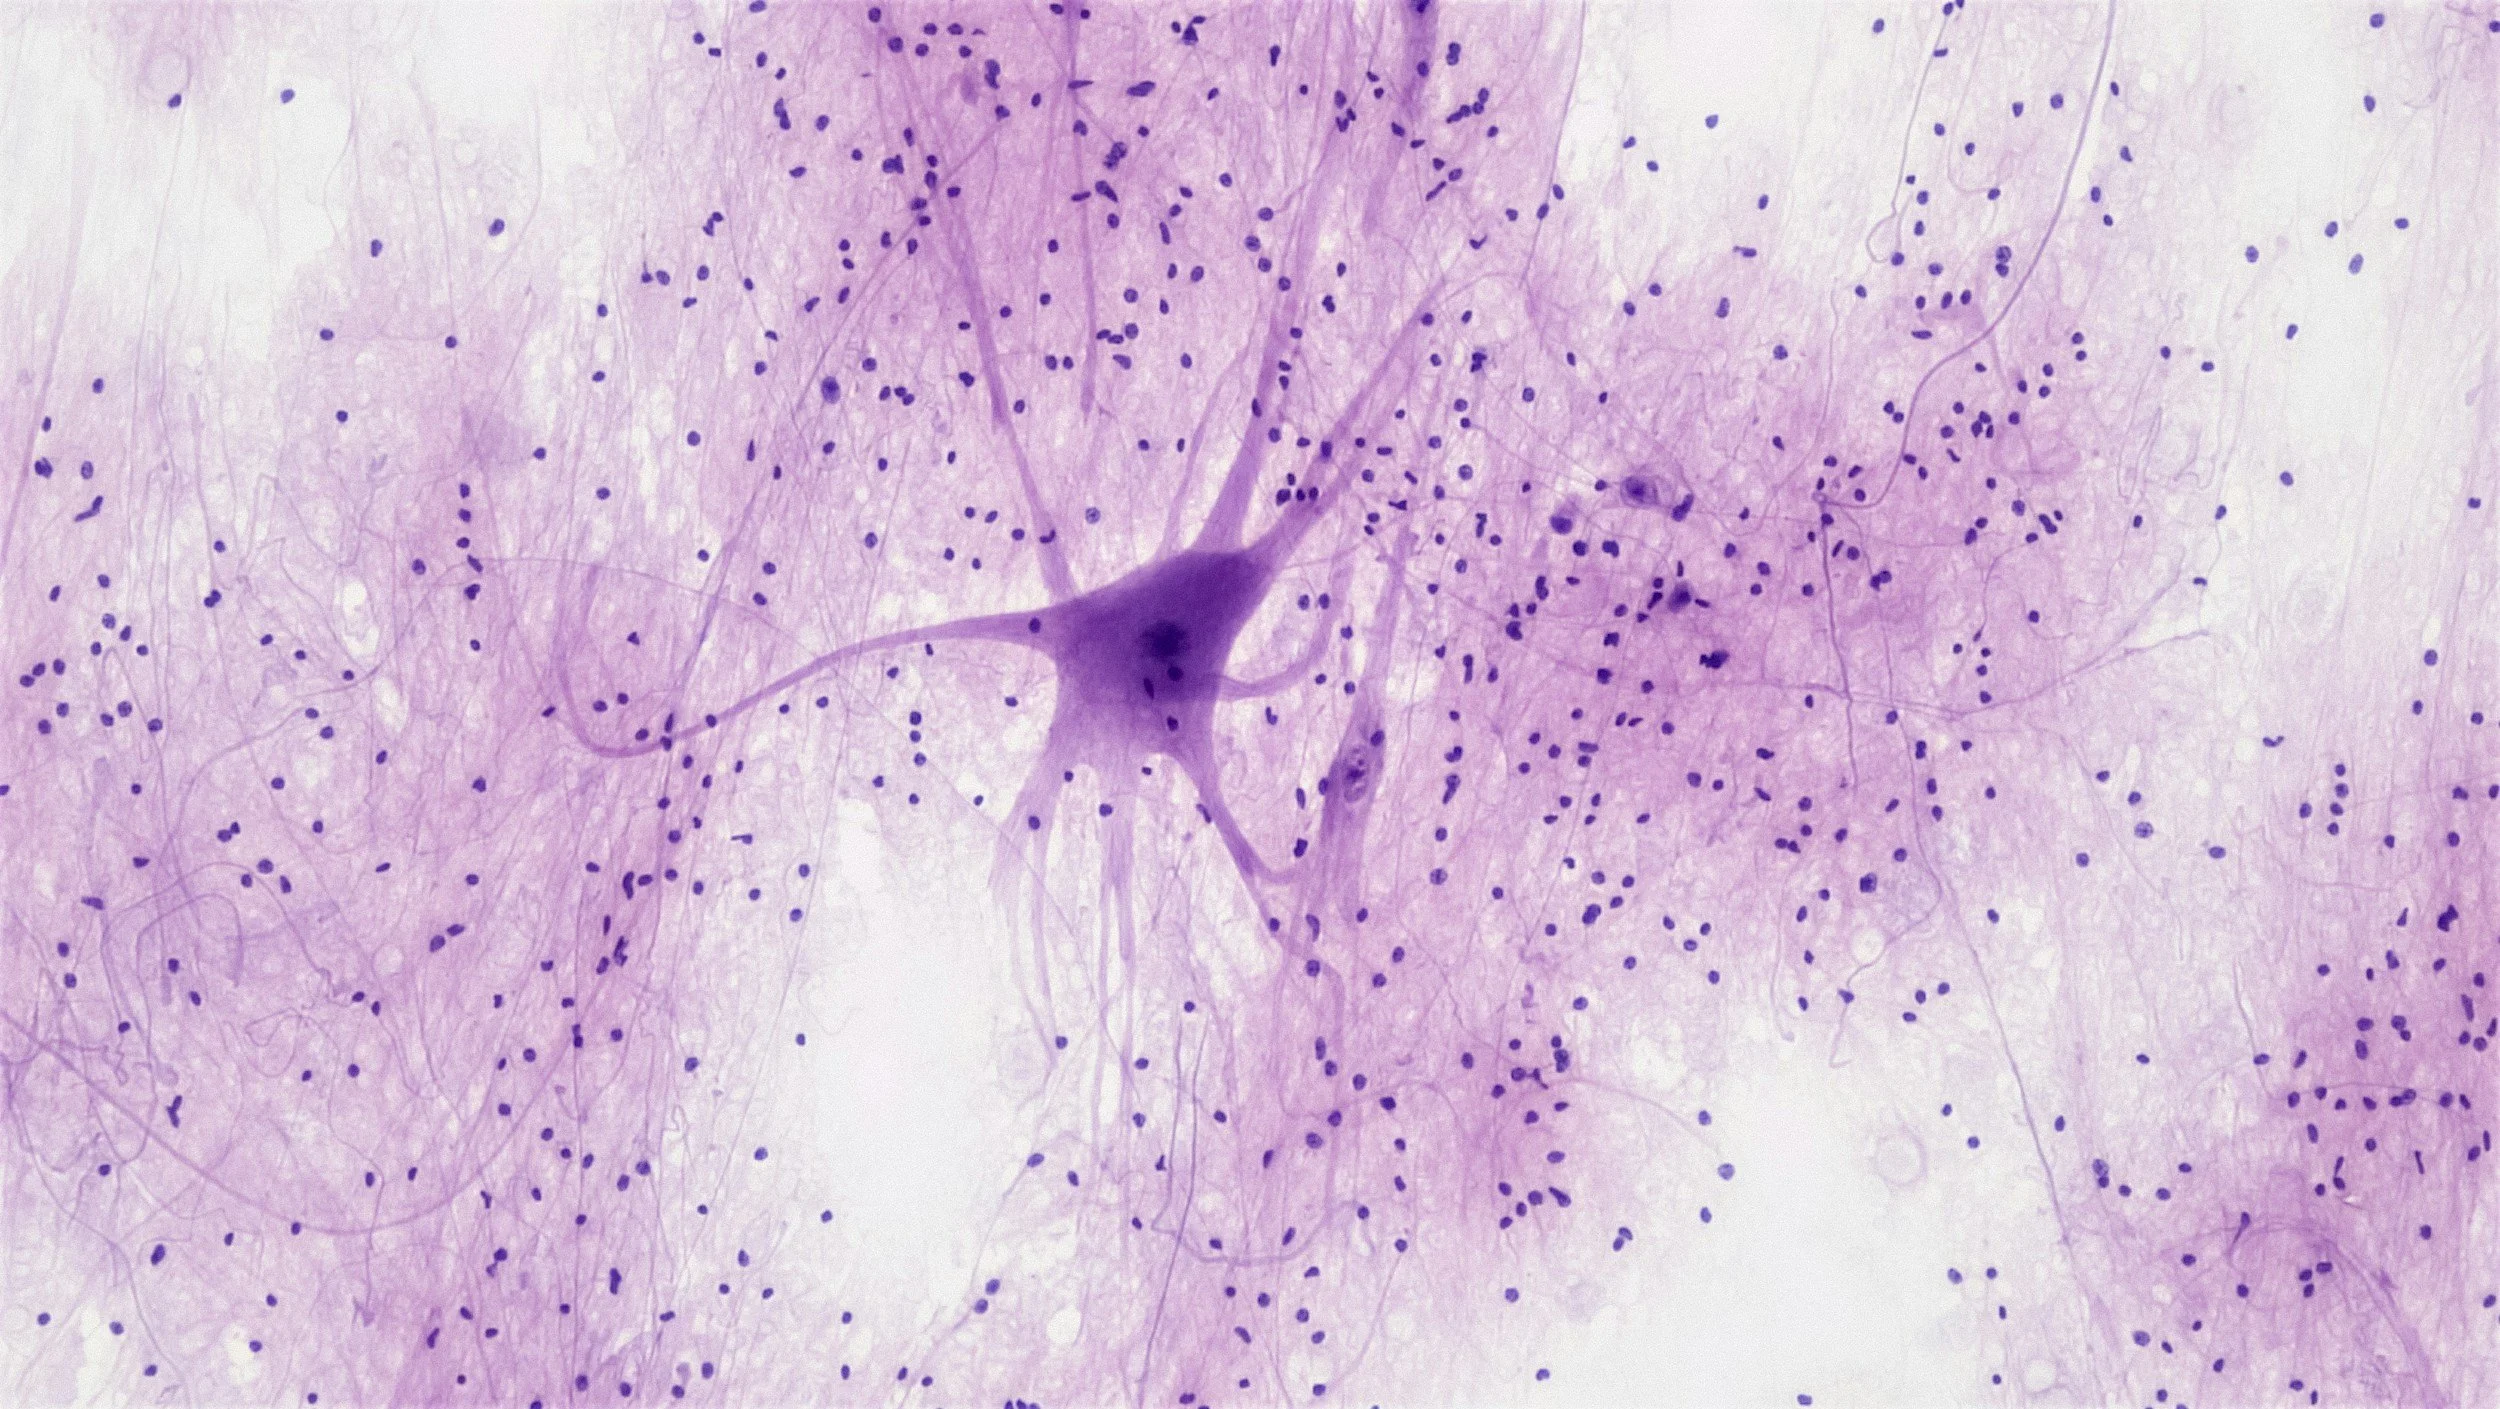

Research in Dr. Xiaobo Mao's laboratory focuses on two core topics: (1) the roles of prion-like proteins and strains in neurodegenerative disorders, including spreading pathways, molecular mechanisms of cell-to-cell transmission, neurotoxicity, and neuroinflammation; (2) the therapeutic developments.

Environmental factors, prion-like protein strains and spreading, immune